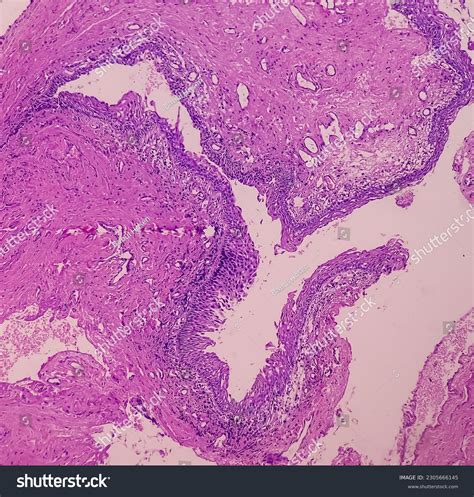

In some cases, a biopsy may be performed to rule out malignant conditions, although Skene duct cysts are typically benign.

• skene duct cyst histology